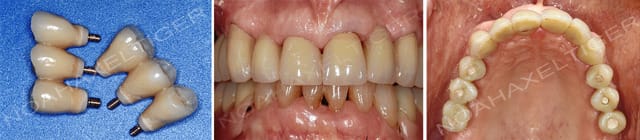

Etape 7 : une fois satisafit des réglages occlusaux et esthétiques, prise d'empreinte et pose des constructions prothétiques finales.

A plus.

Etape 7 ce0k6k - Eugenol

Radio final bhd6mz - Eugenol

Je préfère les constructions transvissées aux scellées. Je ne vois pas l'intérêt de sceller des constructions implantaires plurales. C'est plus compliqué, on ne contrôle pas la fuite éventuelle du matériaux de scellement, la dépose en cas de souci est quasi impossible.

Les cas de périimplantites qui me sont adressés me conforte dans ce choix.

Aprés il y a des cas particuliers ... mais de facon générale et pour les reconstructions implantaires plurales, pour moi, c'est le transvissé en premier choix.